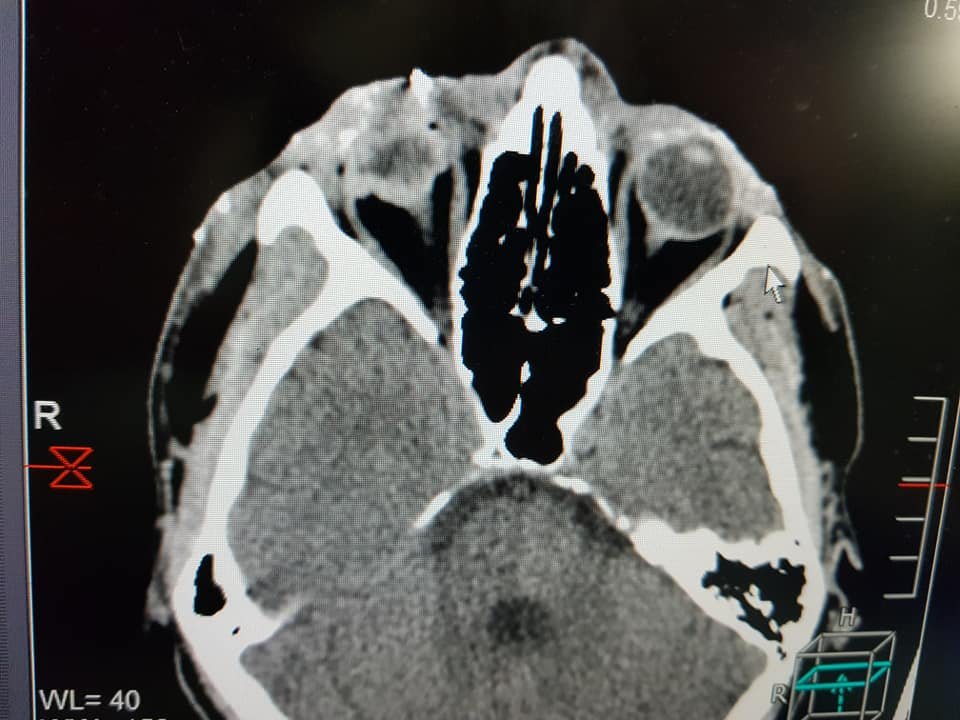

"Андрею 33, солдат из Николаева. Получил ранения сегодня у Водяного. Тяжелое минно-взрывное ранение, проникающее ранение правого глаза, осколочные ранения лица, конечностей. Вся команда врачей Мечникова и офтальмологи ДОКОБ в реанимационном зале. Сделаем все, чтобы Андрей выздоровел", - написал Александр Толубаев, заместитель главврача по оказанию экстренной помощи в больнице Мечникова.

"Утром еще один тяжело ранен. Александру 24, обстрел у Водяного сегодня ночью. Начинается нейрохирургическое вмешательство. Впереди сложная борьба за жизнь", - написал Андрей Толубаев.